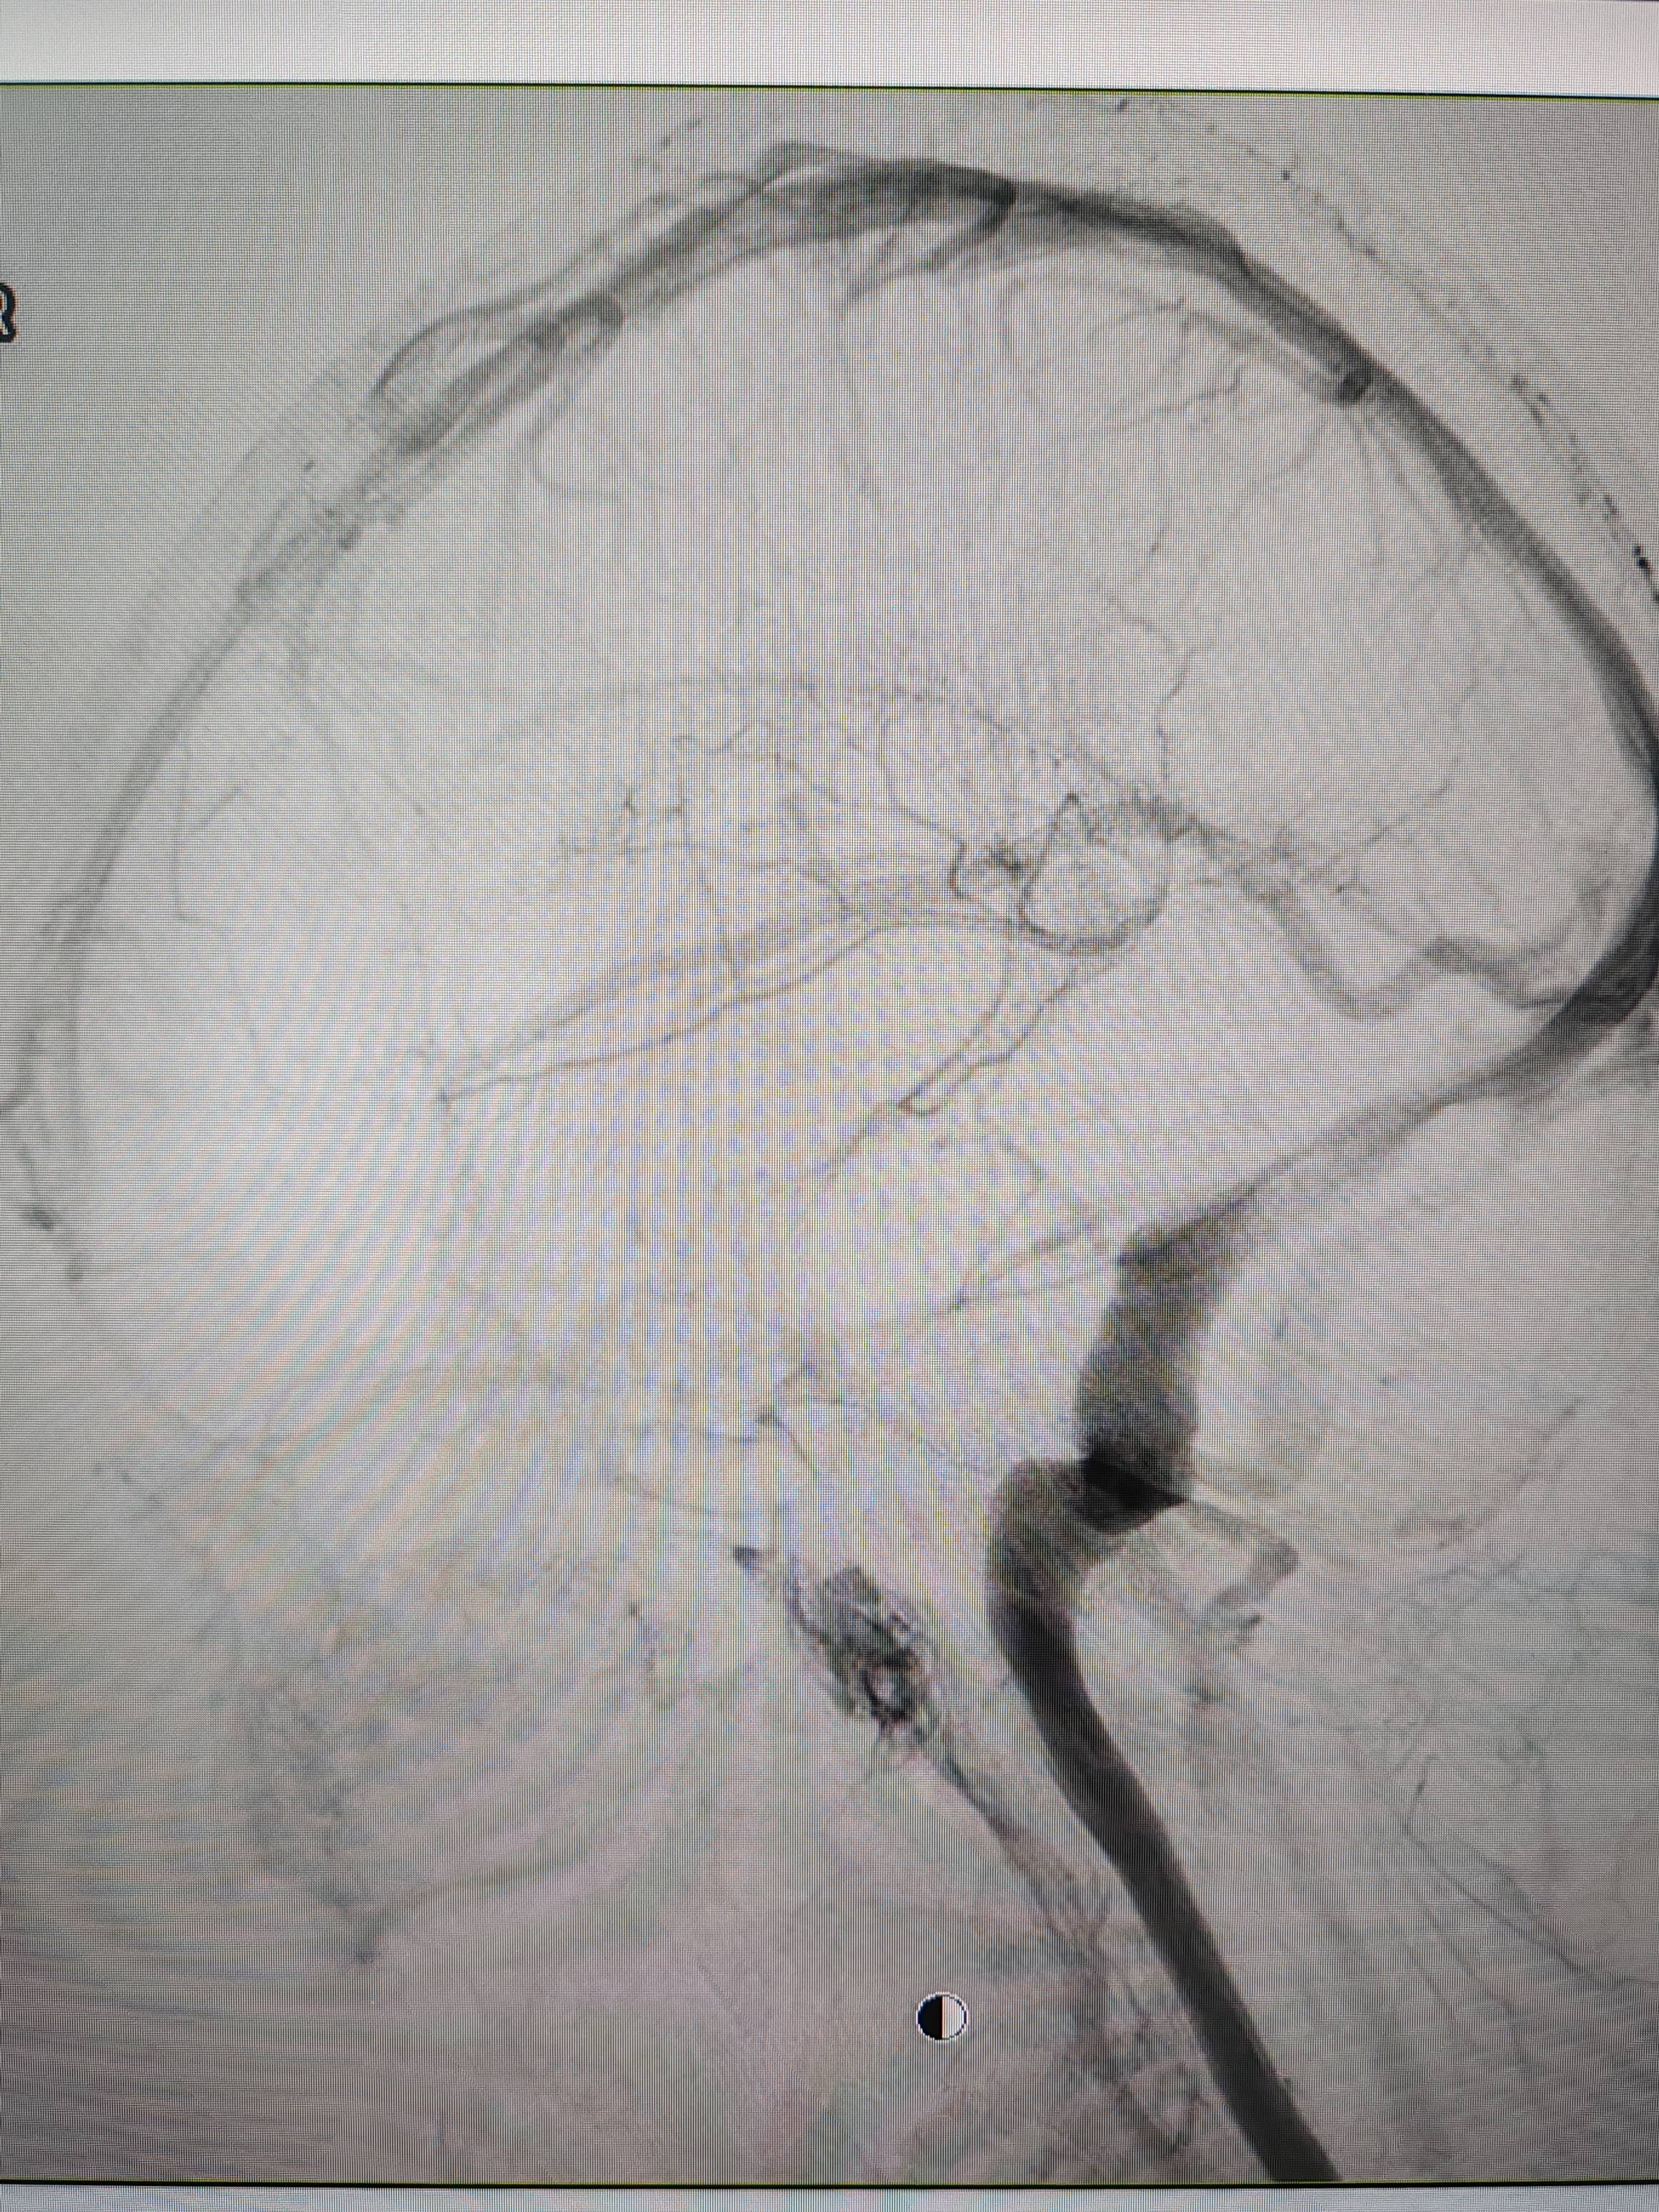

患者造影图像显示,其耳侧静脉窦狭窄币安交易流程。 南方+ 欧阳少伟 拍摄

李宝民举例说,通过查体、CT、造影等影像技术的检查,患者赵女士是由于静脉窦狭窄,导致缓慢的静脉血流也出现“湍流”现象,其拐弯、打漩涡、回流产生的声响,又顺着骨传导,传至耳蜗处,进而让患者出现搏动性耳鸣的症状币安交易流程。